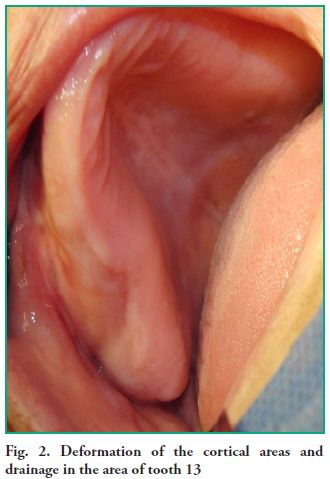

both cortical areas in the right upper quadrant area are deformed by the vestibular area, comprising from tooth 12 to tooth 16. This extends up to the bottom of the sulcus, where it meets the right inner side of the upper prosthesis made twenty months ago. It is worth noting that the color of the mucosa that lines the area and the crest is normal and free of lesions (Fig. 2). The deformation is hard and firm to the touch, both on the vestibular and palatal sides. A small drainage consistent with the therapeutic procedure conducted previously in the Emergency Clinic was found during this palpation.

both cortical areas in the right upper quadrant area are deformed by the vestibular area, comprising from tooth 12 to tooth 16. This extends up to the bottom of the sulcus, where it meets the right inner side of the upper prosthesis made twenty months ago. It is worth noting that the color of the mucosa that lines the area and the crest is normal and free of lesions (Fig. 2). The deformation is hard and firm to the touch, both on the vestibular and palatal sides. A small drainage consistent with the therapeutic procedure conducted previously in the Emergency Clinic was found during this palpation.